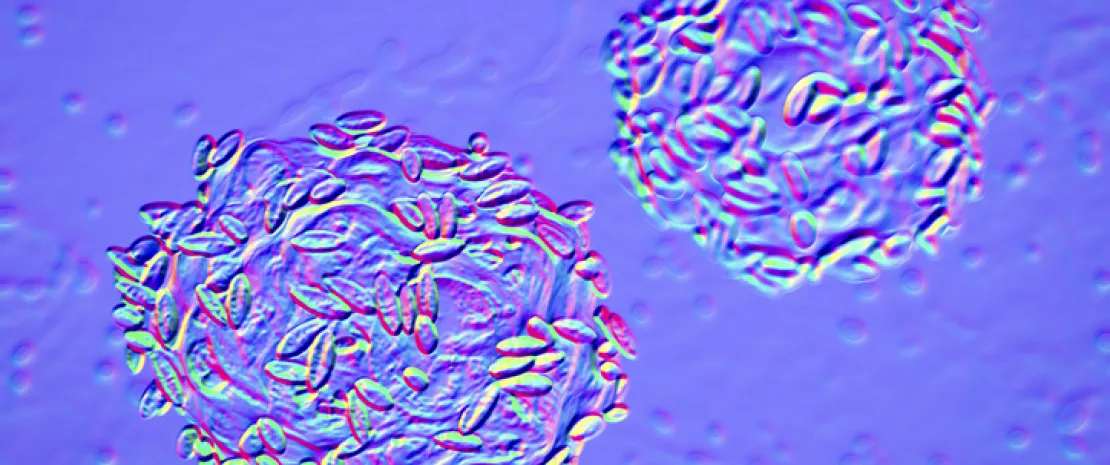

Doğal tipten 10 kat daha yüksek bakterisidal etki

Bu bağlamda yazarlar alan karıştırma yoluyla çeşitli tasarlanmış endolizinler ürettiler. Yazarlar Gardnerella suşu üzerindeki bakterisidal etkiyi doğal tip endolizinlerinkiyle karşılaştırdılar. Rekombinant endolizinlerin bakteriyel etkisi herhangi bir doğal tip enziminkinden 10 kat fazlaydı. 20 Gardnerella suşundan ( (sidenote: G. vaginalis, G. leopoldii, G. piotii ve G. swidsinskii ) ) oluşan bir panele karşı test edildiğinde PM-477 olarak adlandırılan en aktif endolizin, test edilen antibiyotiklere (metronidazol, tinidazol, klindamisin) kıyasla daha üstün etkililik gösterdi. Ayrıca PM-477'nin faydalı lactobacillus bakterileri veya diğer vajinal bakteri türleri üzerinde etkisi yoktu. Yazarlara göre, PM-477 Gardnerella açısından çok seçicidir ve lactobacillus bakterilerini veya diğer vajinal bakteri türlerini etkilemeden dört ana türün her birinin suşlarını öldürmektedir. PM-477'nin etkisi Gardnerella ve lactobacillus'tan oluşan karma kültürlerde mikroskop ile inceleyerek teyit edildi. PM-477 (at 460 µg/mL for 5 h) monokültürde G. vaginalis ve G. swidsinskii hücreleri parçaladı ancak lactobacillus'u etkilemeden lactobacillus ile birlikte karma kültürlerde de bunları selektif olarak parçaladı.